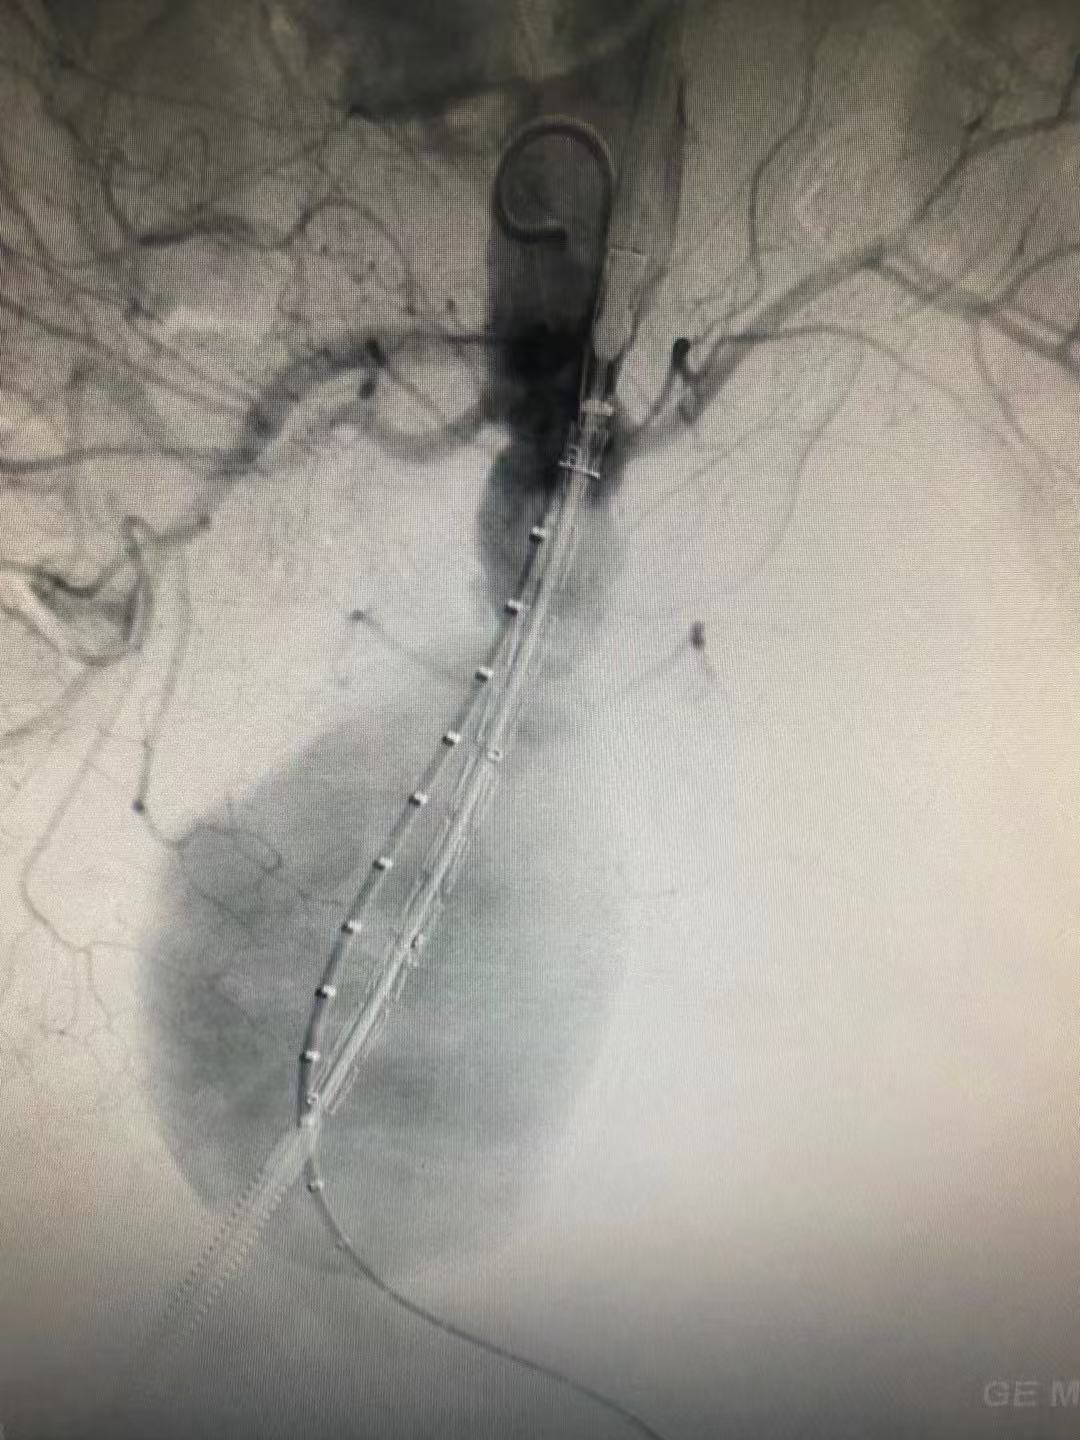

经过最短的术前准备,在介入团队的缜密手术操作和麻醉团队的持续麻醉保障下,顺利为李婆婆植入了支架。术后,李婆婆腹部跳动的包块消失了,标志着这颗威胁着她的「不定时炸弹」成功拆除,随即返回病房接受后续治疗。术后通过 CTA 复查确认,李婆婆的腹主动脉瘤瘤口已完全闭合,血流通畅,恢复情况良好,一家人悬着的心终于落地。

支架植入及球囊扩张形成后